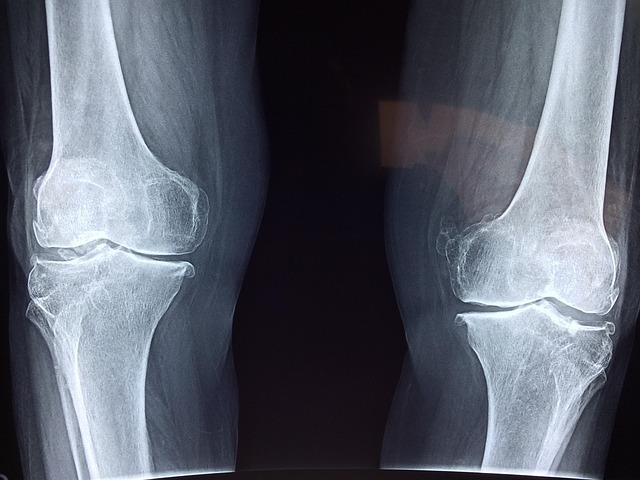

Especialmente útil en fracturas con fragmentos pequeños, imposibles de reparar con métodos tradicionales.

Ya superó un ensayo clínico riguroso con más de 150 pacientes, logrando una unión perfecta de los fragmentos óseos.